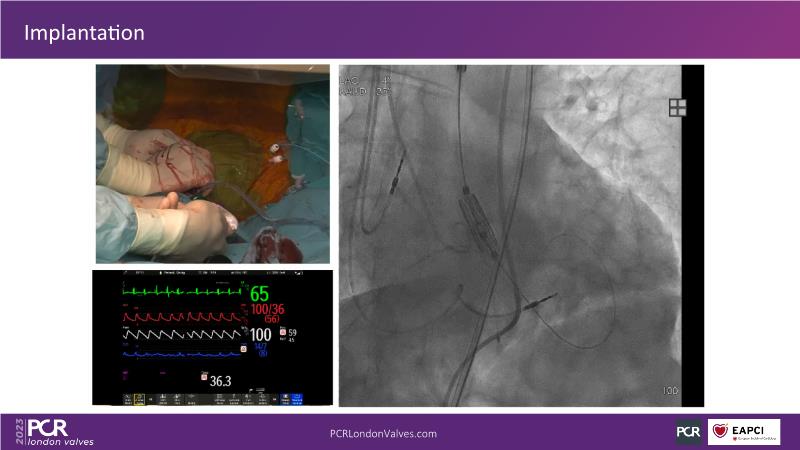

In this session, discover the key features and benefits of next-generation transcatheter heart valve technology. Gain insights into managing bicuspid and valve-in-valve interventions, and understand the procedural and clinical significance of intermediate and XL sizes in addressing unmet clinical needs.

- Learn about the next generation transcatheter heart valve technology key features, procedural and clinical benefits

- Understand the importance of predictable and precise commissural and coronary alignment for lifetime management of TAVI patients